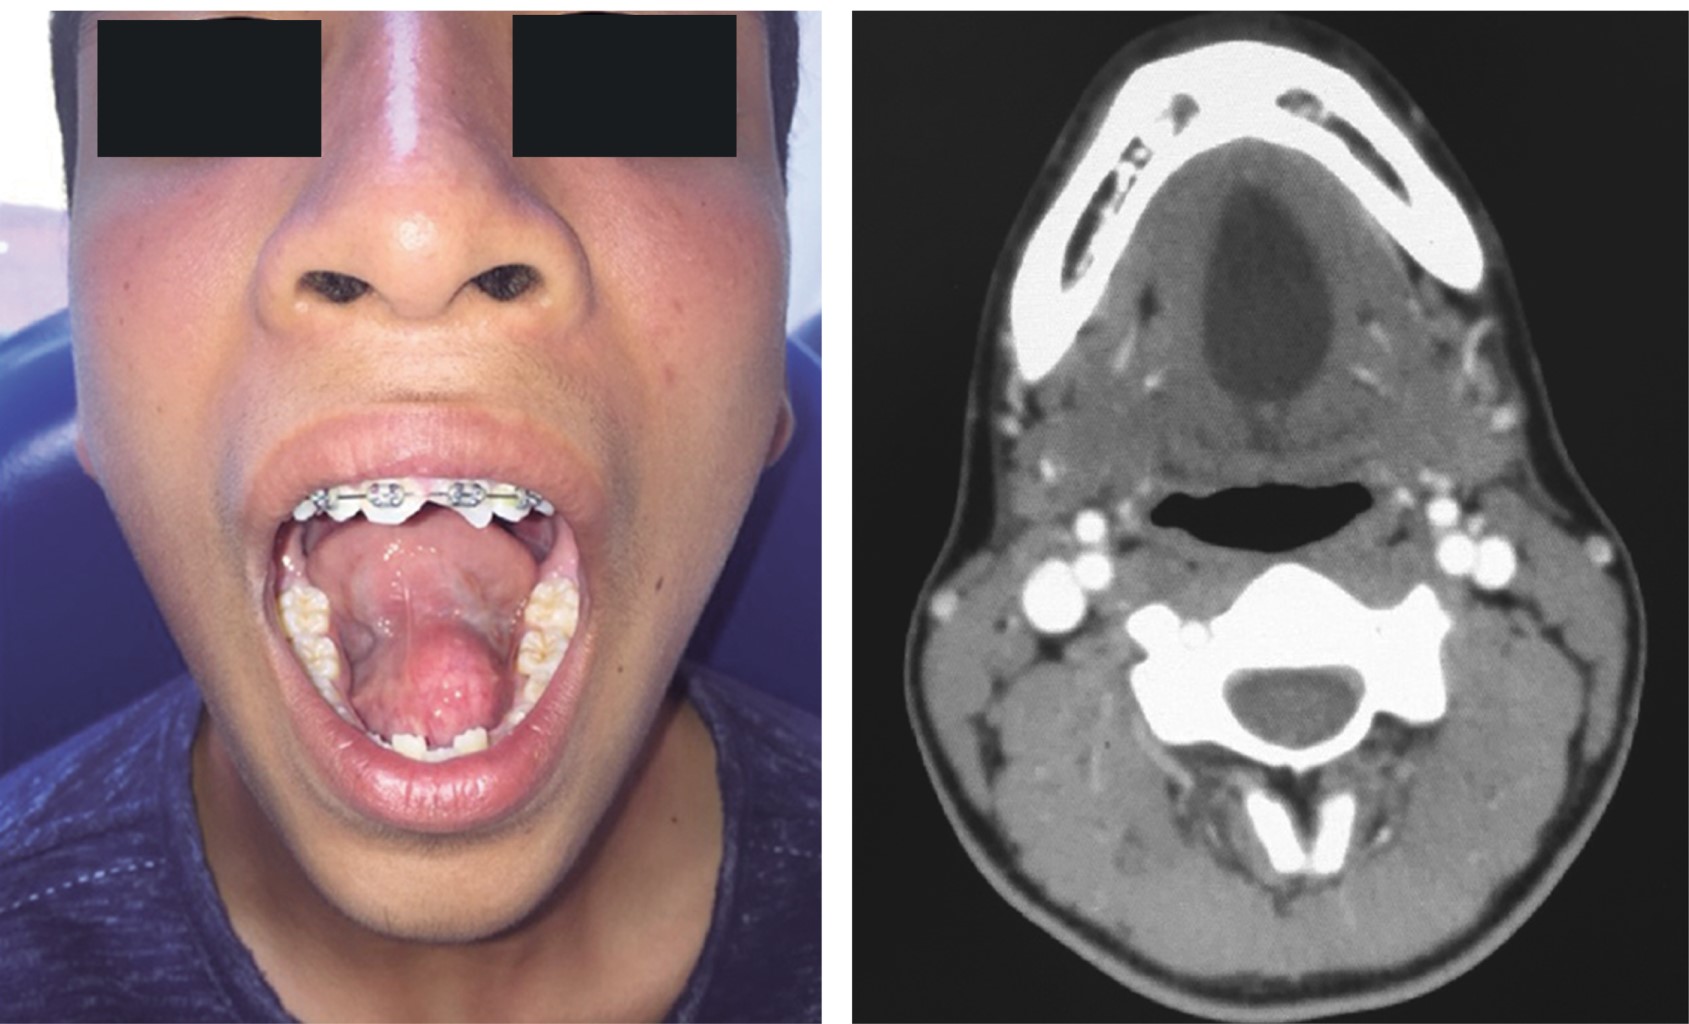

Masculino de 14 años de edad, referido del Hospital de Cardel tras iniciar con aumento de volumen sublingual de seis meses de evolución asintomático, sin cambios en el tono o intensidad de voz y sin datos de obstrucción de la vía aérea, el cual alcanza su tamaño máximo de aproximadamente 4 × 4 cm a los seis meses del inicio de la sintomatología. A la exploración física se observa un aumento de volumen bien delimitado en el piso de la boca, sin datos de secreción de algún tipo, con ligera proptosis de la lengua y sin datos de obstrucción de la vía aérea, ni datos de desaturación por oximetría de pulso. Tomográficamente en la TC simple y contrastada de cráneo y macizo facial, en los cortes axiales, sagitales y coronales, se observa lesión hipodensa, circunscrita y bien delimitada en el espacio sublingual, sin reforzamiento de medio de contraste o aparente involucro de vasos. Para el tratamiento se realiza, bajo anestesia general balanceada, abordaje intraoral previa infiltración de lidocaína con epinefrina al 2% 1:100,000 para bloqueo del nervio lingual y alveolar inferior bilateral, se incide con hoja de bisturí #15, plano de mucosa del piso de la boca, y con disección roma se eleva colgajo mucoso hasta localizar la cápsula de la lesión quística, se realiza enucleación de la lesión y exéresis de la misma, obteniendo como resultado una masa firme de 4 × 4 cm con contenido similar a queratina, se lava lecho quirúrgico con abundante solución salina al 0.9% y se realiza cierre de abordaje intraoral mediante poliglactina 910 (Vicryl) 4-0. Reporte histopatológico: quiste epidermoide (Figura 3).

Paciente masculino de 29 años de edad, el cual se presenta en consulta para valoración de aumento de volumen en región sublingual. A la exploración clínica se observa aumento de volumen en región submental que se hace más evidente de manera intraoral a la elevación de la lengua de aproximadamente 6.5 cm de diámetro, el cual a la palpación no está adherido a planos profundos, libremente desplazable. Se realiza biopsia por aspiración y punción por aguja fina (BAAF), obteniendo material líquido similar a la queratina, por lo que se decide realizar TC simple y contrastada de cráneo y macizo facial. Se observa presencia de lesión hipodensa bien delimitada que abarca el espacio submental y sublingual, en donde no se observa dependencia de vasos ni infiltración a tejidos adyacentes, la cual se encuentra sobre el músculo genihioideo. Se decide realizar exéresis de la lesión bajo anestesia general balanceada, con un abordaje intraoral, previa infiltración de lidocaína con epinefrina al 2% 1:100,000, se bloquea el nervio lingual y alveolar inferior bilateral, para incidir en piso de la boca del lado derecho, y realizar disección roma a lo largo de la cápsula para enuclear la lesión, se elimina pedículo de unión y se obtiene un espécimen de 6.5 × 4 cm, bien delimitado por su cápsula, se realiza lavado de lecho quirúrgico con solución salina al 0.9% y se cierra abordaje intraoral a expensas de poliglactina 910 (Vicryl) 4-0. Resultado de estudio histopatológico: quiste epidermoide de piso de la boca (Figura 5).